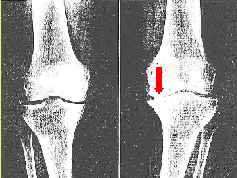

The OBL investigates mechanisms of post-traumatic osteoarthrosis. The research, funded by the CDC, involves the prevention of acute injuries that may lead to this disease. We investigate methods of early diagnosis and intervention into the disease process. Researchers focus on acute injuries, such as bone bruises, cell death, and cartilage matrix damage using human cadavers, in vivo animal models, and in vitro explanted tissues in these studies. The picture to the left is a radiograph showing a clinical, end-stage disease of the knee.